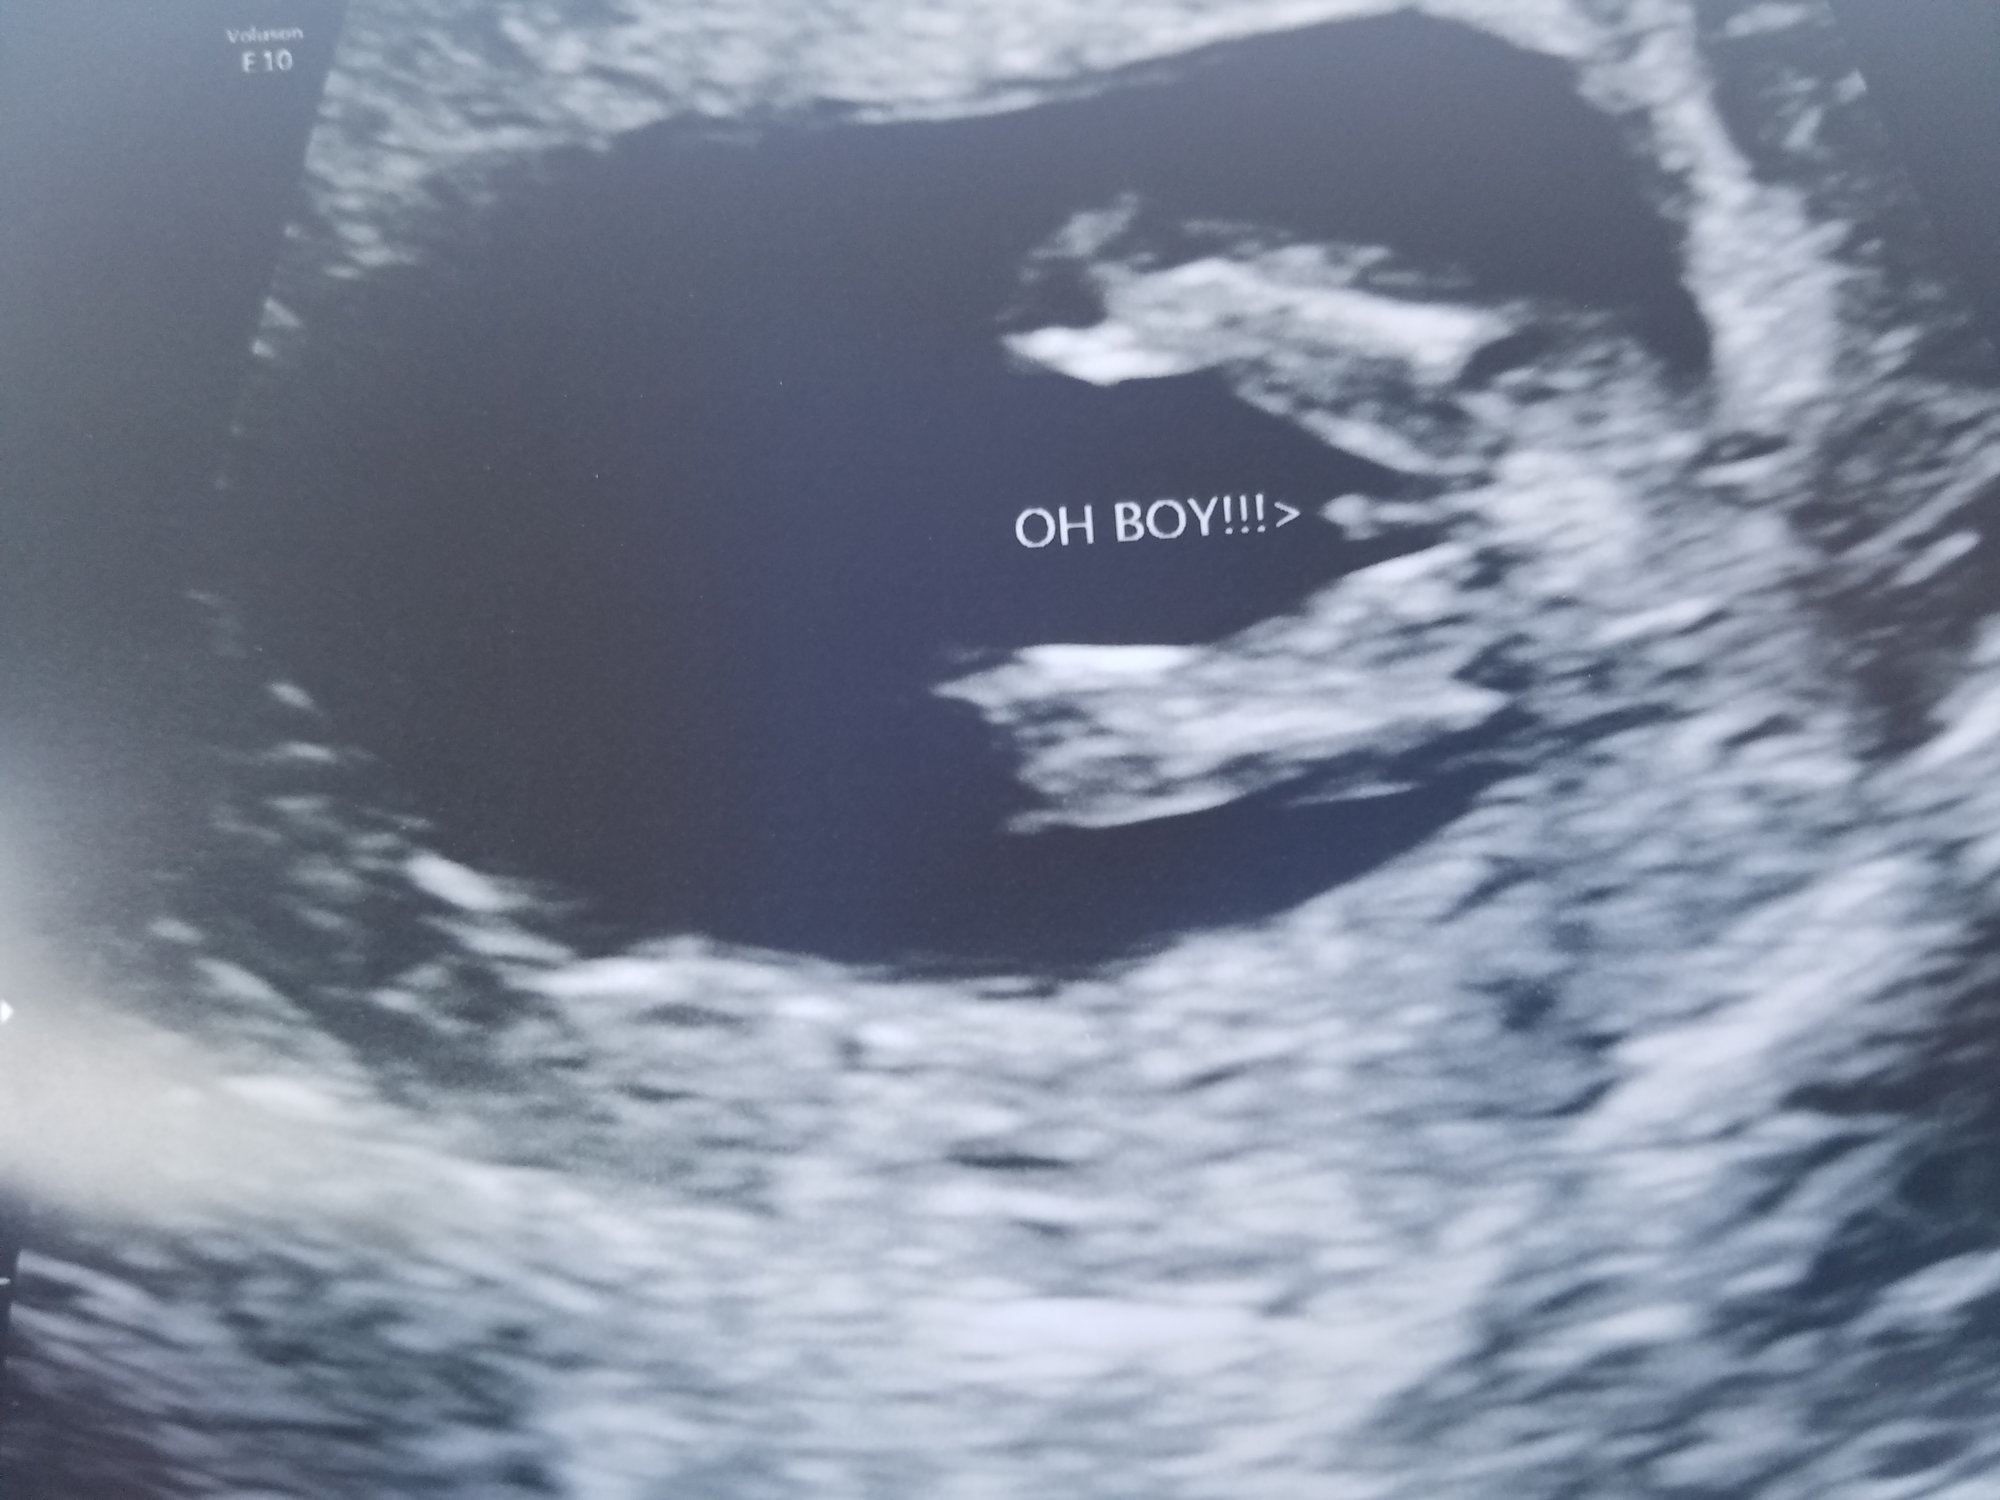

I had this done last Thursday when I was 14wks4-5days at my MFM doctors office the tech said boy other women have said it could be the cord but I feel like the cord wouldve been much thicker and wider.

1: it is a bit early for full development. 2: I would trust the trained professional tech over "other women" and internet strangers. 3: you will have an anatomy scan soon, you will get better answer then.